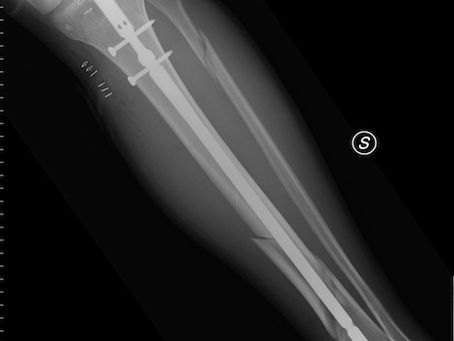

Compétences